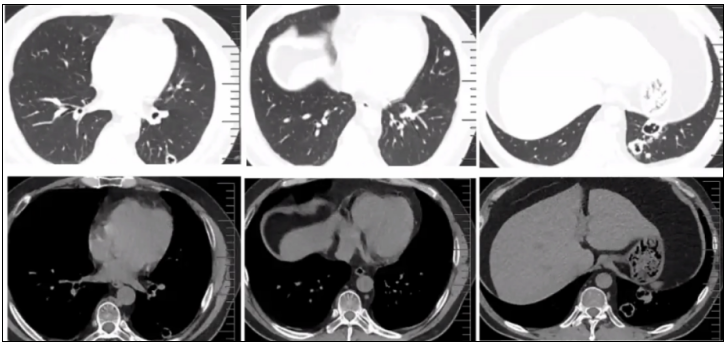

病例4:女性患者,51岁,右锁骨上窝肿物10月余,咳嗽1月余。胸部CT可见肺部阴影,锁骨上肿大淋巴结(图13),同时检测到马尔尼菲篮状菌和曲霉;组织培养提示为混合性真菌感染。

图片

图13  TSM患者肺部影像学表现

病例5:男性患者,39岁,头痛1小时,无太多症状。体检发现肺部多发结节影2月余,可见空洞,内有一不规则物(图14)。经皮肺穿刺活检提示马尔尼菲篮状菌和隐球菌,确诊为混合感染。

图14  TSM患者肺部影像学表现

病例6:男性患者,19岁,反复发热、咳嗽、咳痰5月余。胸部CT见右下肺大片实变影,中间有支气管气象(图15),培养和组织活检均证实为马尔尼菲篮状菌,后续累及气道,导致气道软化和塌陷,预后不良。

图15  TSM患者肺部影像学表现

病例7:男性患者,21岁,反复咳嗽、咳痰、发热2年。胸部CT可见双肺散在结节状阴影,既往曾诊断结核,但在左上肺有一巨大的厚壁空洞,内壁不光整(图16),该患者是马尔尼菲篮状菌和曲霉的混合感染。

图16  TSM患者肺部影像学表现